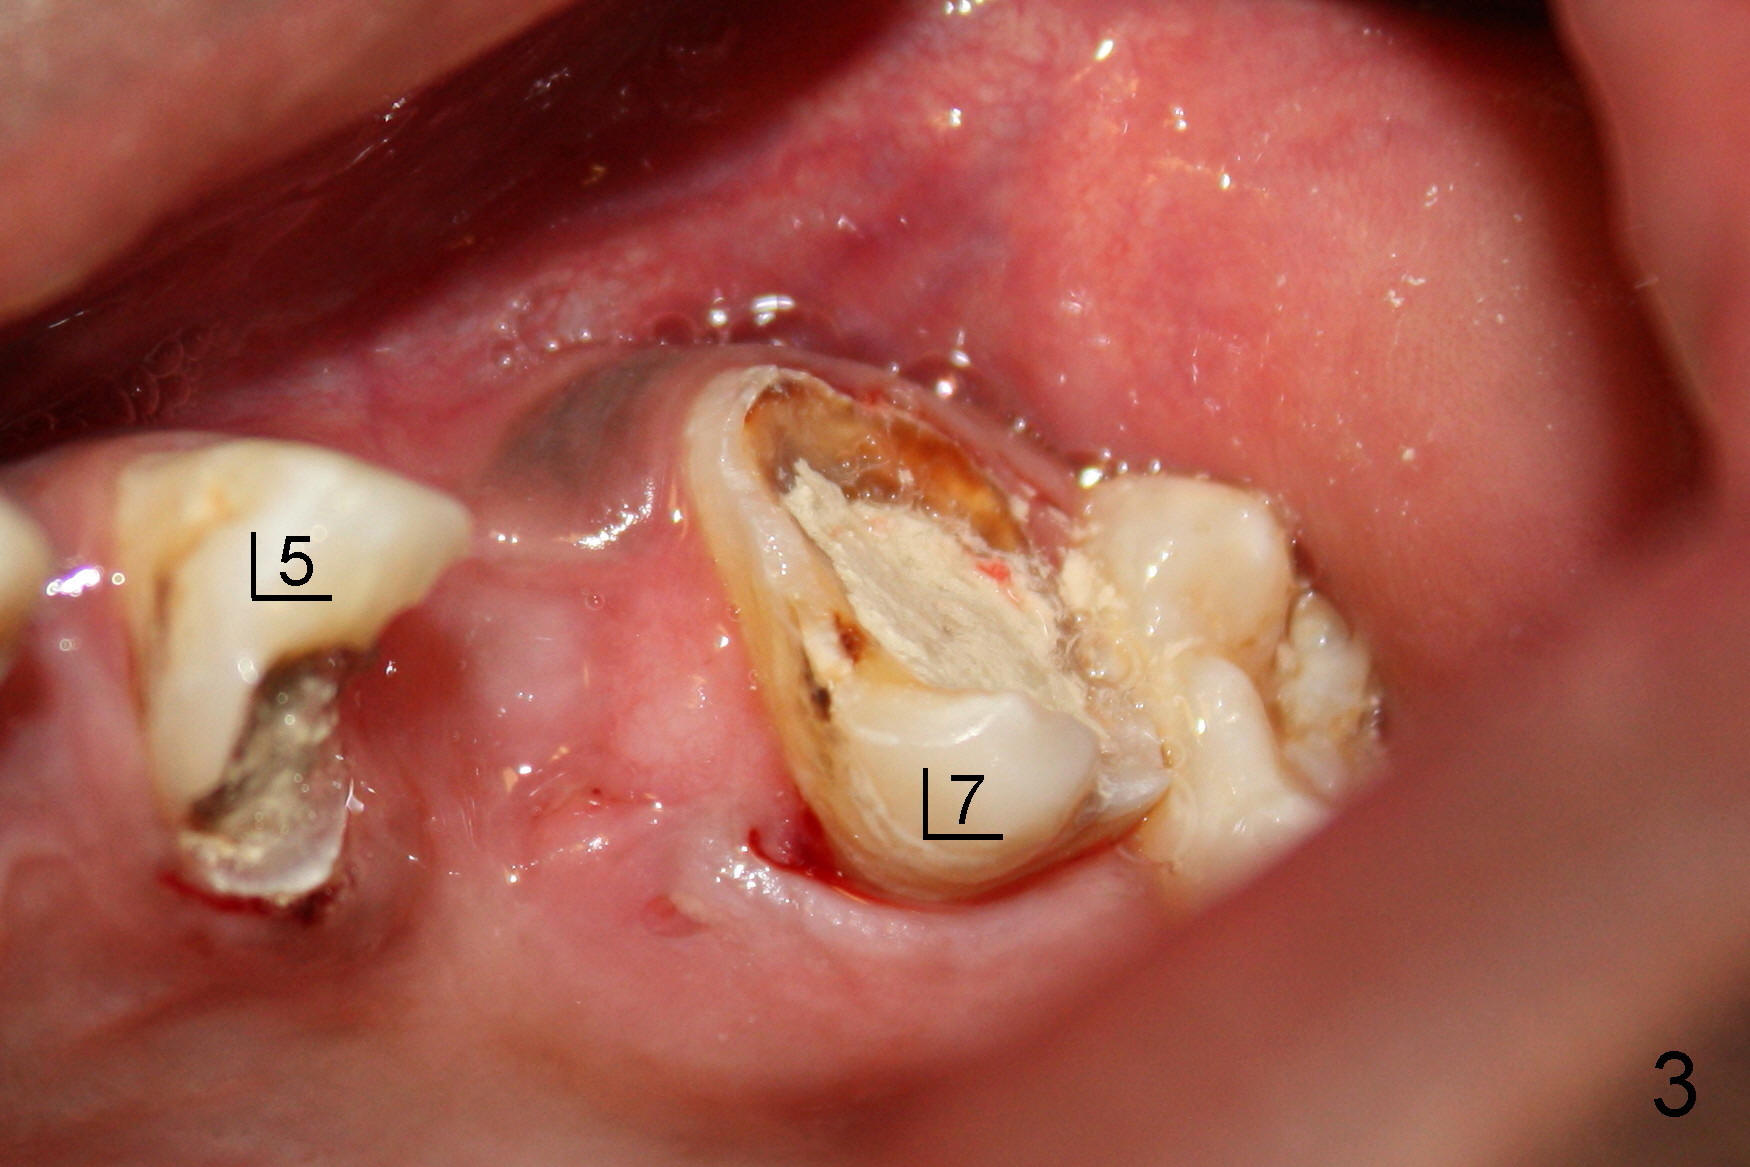

今天给一位二十四岁黑人做根管治疗:左上五(完成:三个根管)和七(开始)(图三),由于他的牙齿大,龋齿也大,根管口特别好找,包括MB2(图一),MB1,DB,P 扩大至二十号hand file;MB2扩大至20/.06 rotary file(还使用#2 Gates-Glidden file扩大MB2根管口)。由于时间不够,病人累了,paper point吸干根管后,拍摄图一(mirror view)。